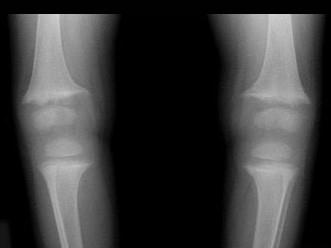

男,2岁,关节浮肿,请结合图像,选出最可能的诊断 ( )A、维生素C缺乏症B、维生素D过多症C、MPSD、维生素D缺乏症E、肾性骨病

问题 男,2岁,关节浮肿,请结合图像,选出最可能的诊断 ( )

选项 A、维生素C缺乏症 B、维生素D过多症 C、MPS D、维生素D缺乏症 E、肾性骨病

答案 E